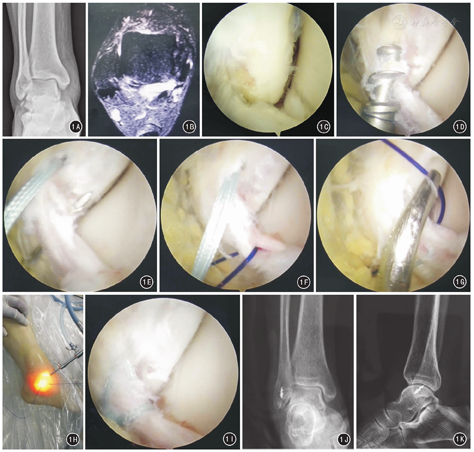

所有患者顺利完成手术,手术时间30~75 min(46.27±7.83)。经术中镜下探查均确诊为单纯距腓前韧带损伤,均无跟腓韧带损伤。术后切口均获一期愈合,无一例出现神经、血管、肌腱损伤等并发症。36例患者随访12~25(14.63±6.80)个月。末次随访时:踝关节外观恢复满意,无感觉过敏现象及瘢痕触痛,踝关节恢复正常活动,踝关节抽屉试验阴性,未出现患肢肌肉萎缩,无关节痛及关节不稳情况,均恢复正常行走步态;VAS、AOFAS及Olerud-Molander足踝部评分分别为(0.31±0.14)、(90.40±9.62)、(88.71±7.38)分,与术前比较差异均有统计学意义(P值均<0.05),见表1。依据AOFAS评分,踝功能优34例,良2例,优良率100%;依据Olerud-Molander足踝部评分,优31例,良5例,踝功能优良率100%。典型病例见图1。

选择踝关节水平线、胫前肌腱内侧5 mm水平为进针点,向腔内注射20 mL生理盐水以充盈踝关节腔。在进针点做一长约5 mm切口,直钳扩充通道后,插入直径2.7 mm或4.0 mm 30°关节镜头,探查踝关节腔内情况,并在镜头监视下在第三腓骨肌外侧建立标准踝关节前外侧入路。清理踝关节腔内血块、游离体、软骨碎片及增生的滑膜,注意保持踝关节囊的完整性。探查距腓前韧带及外踝骨折情况,清理骨折断端间的积血及填充的软组织,显露骨折端及距腓前韧带。在腓骨尖下方1.0 cm、前方3.0 cm处在硬膜外穿刺针定位下建立距下关节前侧手术入路,插入刨刀头以彻底显露距腓前韧带及腓骨骨折端。术中需确认距腓前韧带的完整性和连续性,并探查跟腓韧带后,先采用直径1.2 mm克氏针在距腓前韧带腓骨止点及其周缘水平钻孔打磨,再从距下关节前侧入路打入1~2枚直径3.5 mm的双线或四线锚钉。在关节镜监视下,硬膜外穿刺针从靠近腓骨侧的距腓前韧带中间垂直穿入。在穿刺针内插入强生PDS线,穿过距腓前韧带后,拔出硬膜外穿刺针。在腓骨尖下1 cm建立距下关节中间入路,将PDS线缠绕距腓前韧带半周后,从此处穿出;将锚钉尾端的4股线从距下关节中间入路穿出,PDS线与锚钉中的一股线进行结扎,抽出PDS线。以同样方法再将锚钉中剩余两股线中的一股穿过距腓前韧带。跖屈踝关节,调整好韧带的张力后,复位骨折,并成对结扎锚钉的四股缝线。如合并跟腓韧带损伤,则需要一并行镜下跟腓韧带缝合固定。